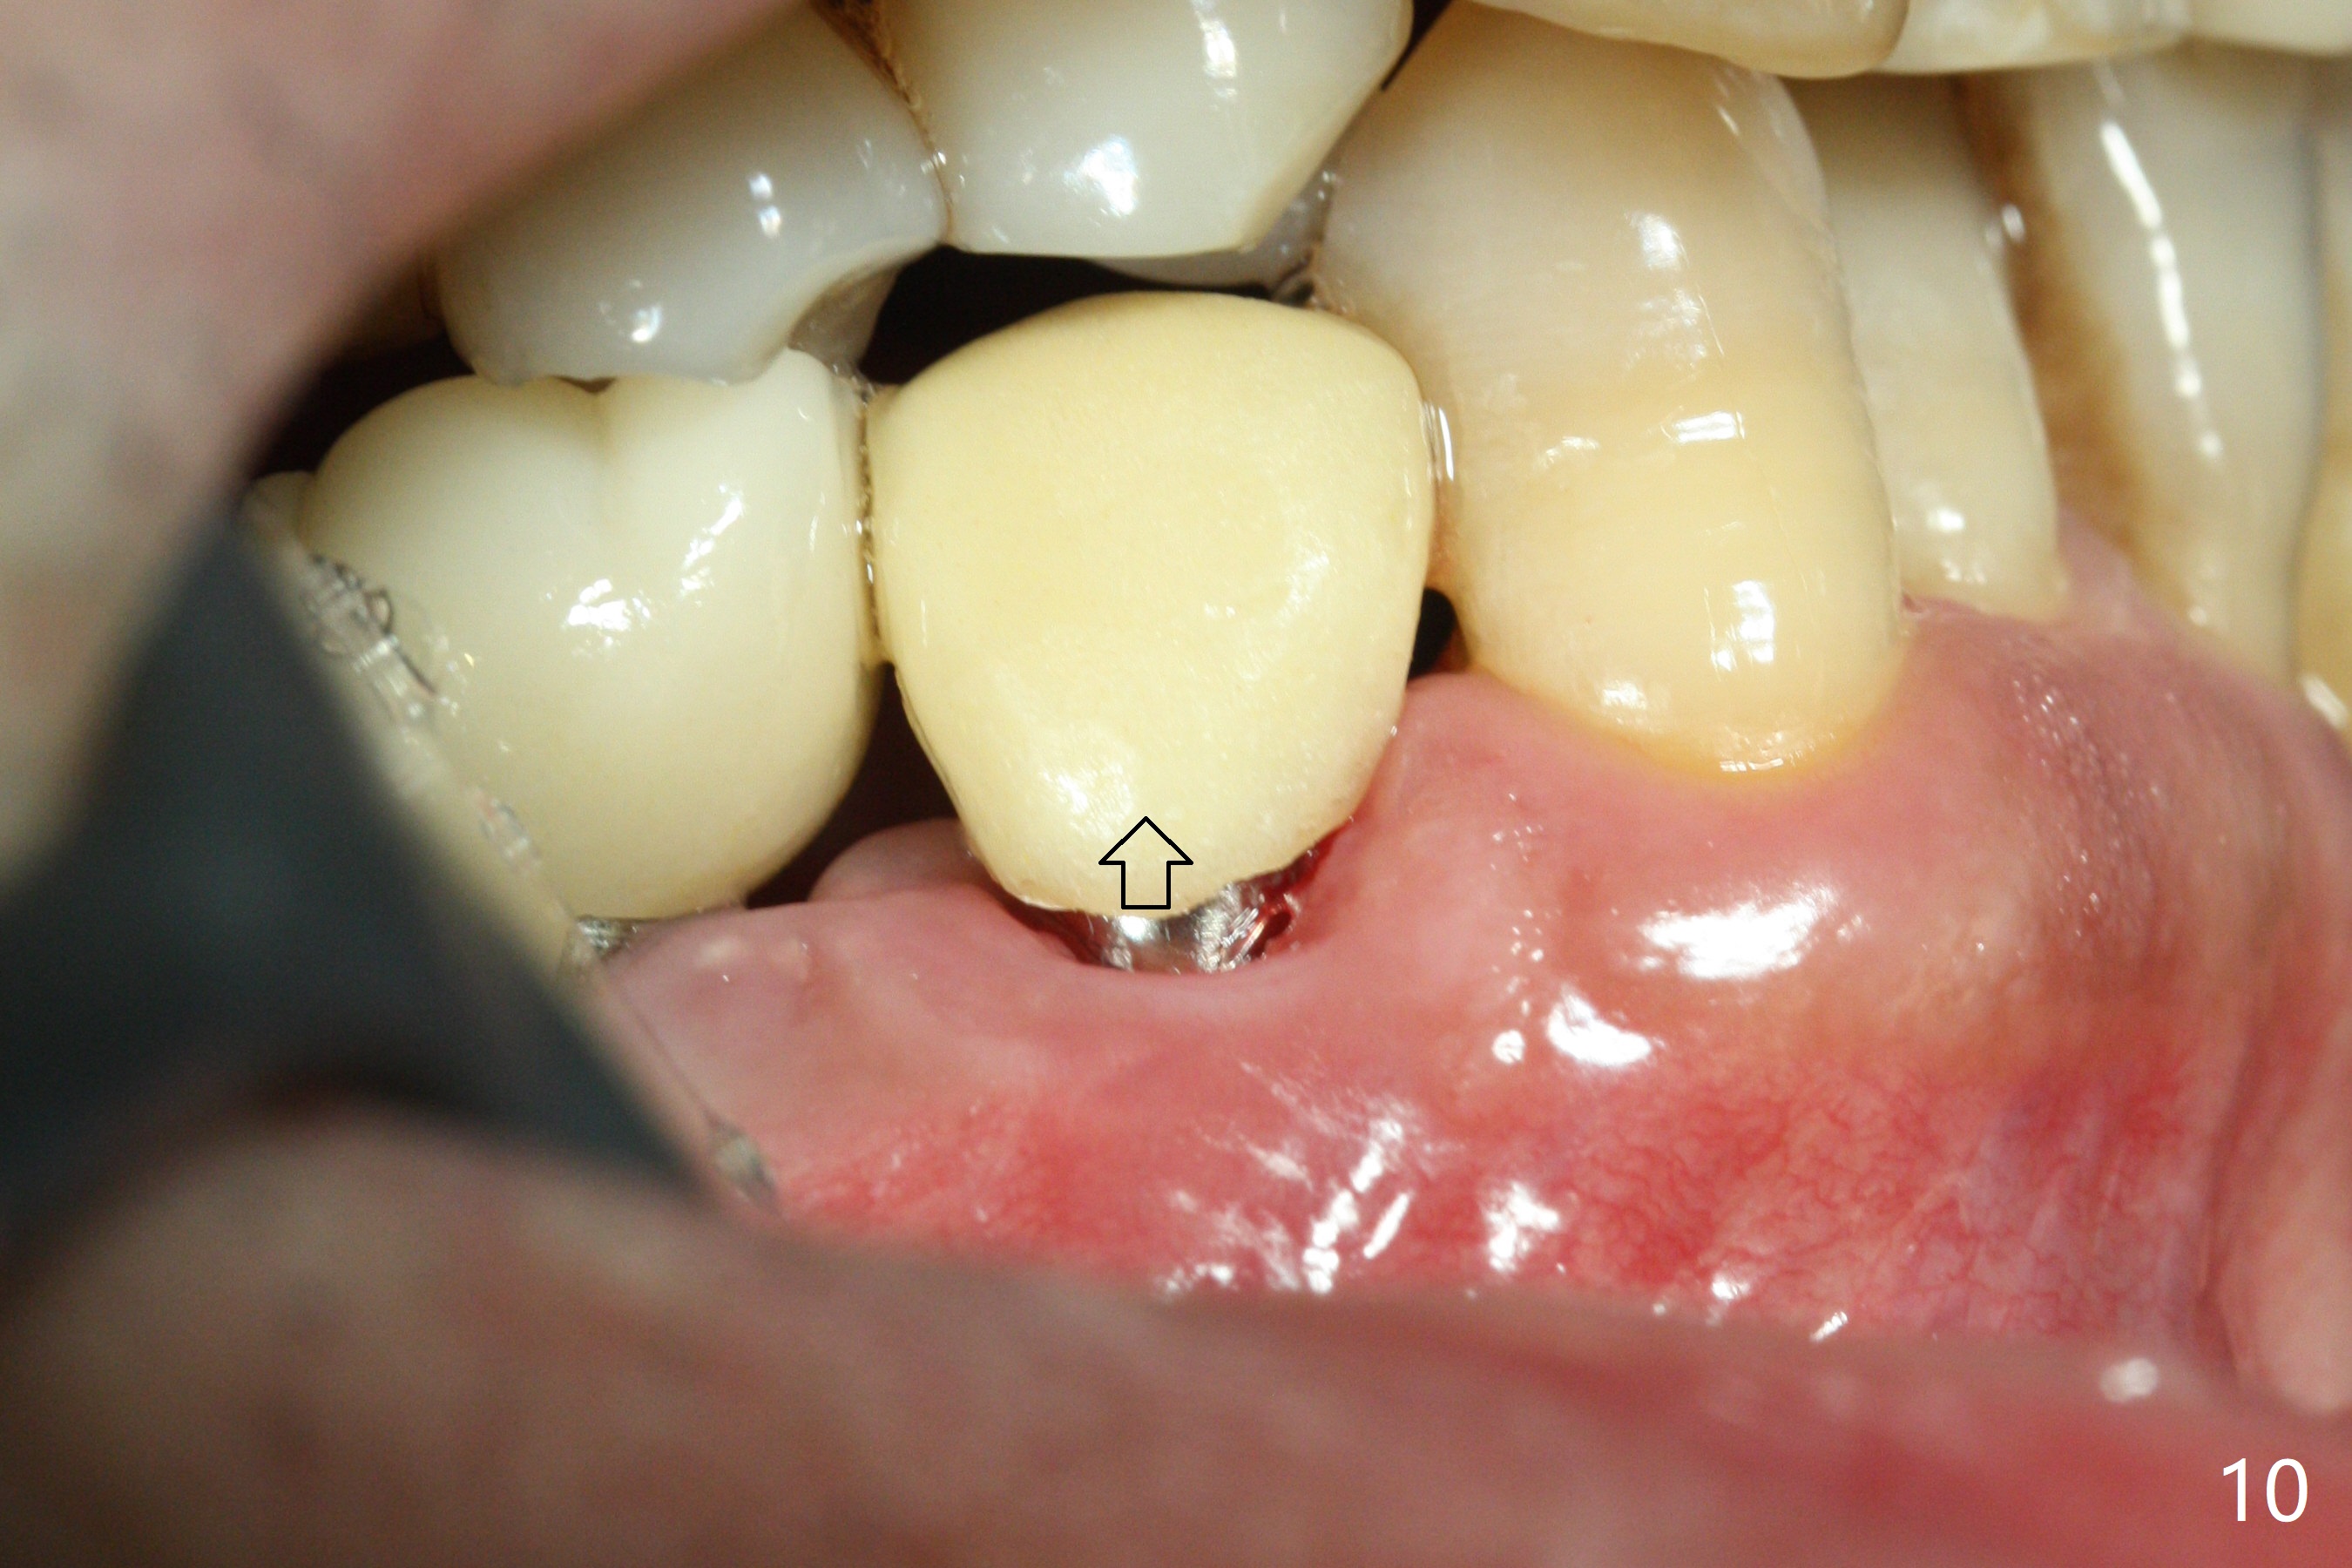

The affected tooth (#28) has buccal gingival recession (Fig.1). As expected, the buccal plate is found low after extraction. Osteotomy is established in the lingual slope of the socket with 1.5 mm drill for 13 mm (Fig.2,3). Following use of Magic Drill 3.3 mm for 13 mm, a 4x11 mm dummy implant is incompletely seated (Fig.4); it is also close to the Mental Loop (Fig.4 red line). After use of Final Drill, a 4x9 mm IBS implant is placed 4 mm and 2 mm subgingival buccal and lingual, respectively (Fig.5) with a large buccal gap (Fig.6 (40 Ncm)). After placement of allograft in the peri-implant space (Fig.7 *), a 4.5x5.7(4) mm abutment is placed (A). A piece of gauze is placed in the remaining buccal space prior to provisional fabrication (Fig.8 *). The space occupied by the gauze is later filled with collagen plug before provisional seating. The gingiva is healthy around the provisional 12 days postop (Fig.9). To reduce buccal gingival recession, the buccal margin of the provisional is shortened 4.5 months postop (Fig.10 arrow). PA taken 5.5 months postop is shown with the implant at 31. The lingual gingiva is erythematous, edematous, and recessive with +BOP and deep pockets 14 months postop (Fig.11). It appears that the small and short implant is not favorable for healing. The infected implant is removed with the missing buccal plate; bone graft is placed 15 months postop (7 months post cementation, Fig.12,13).